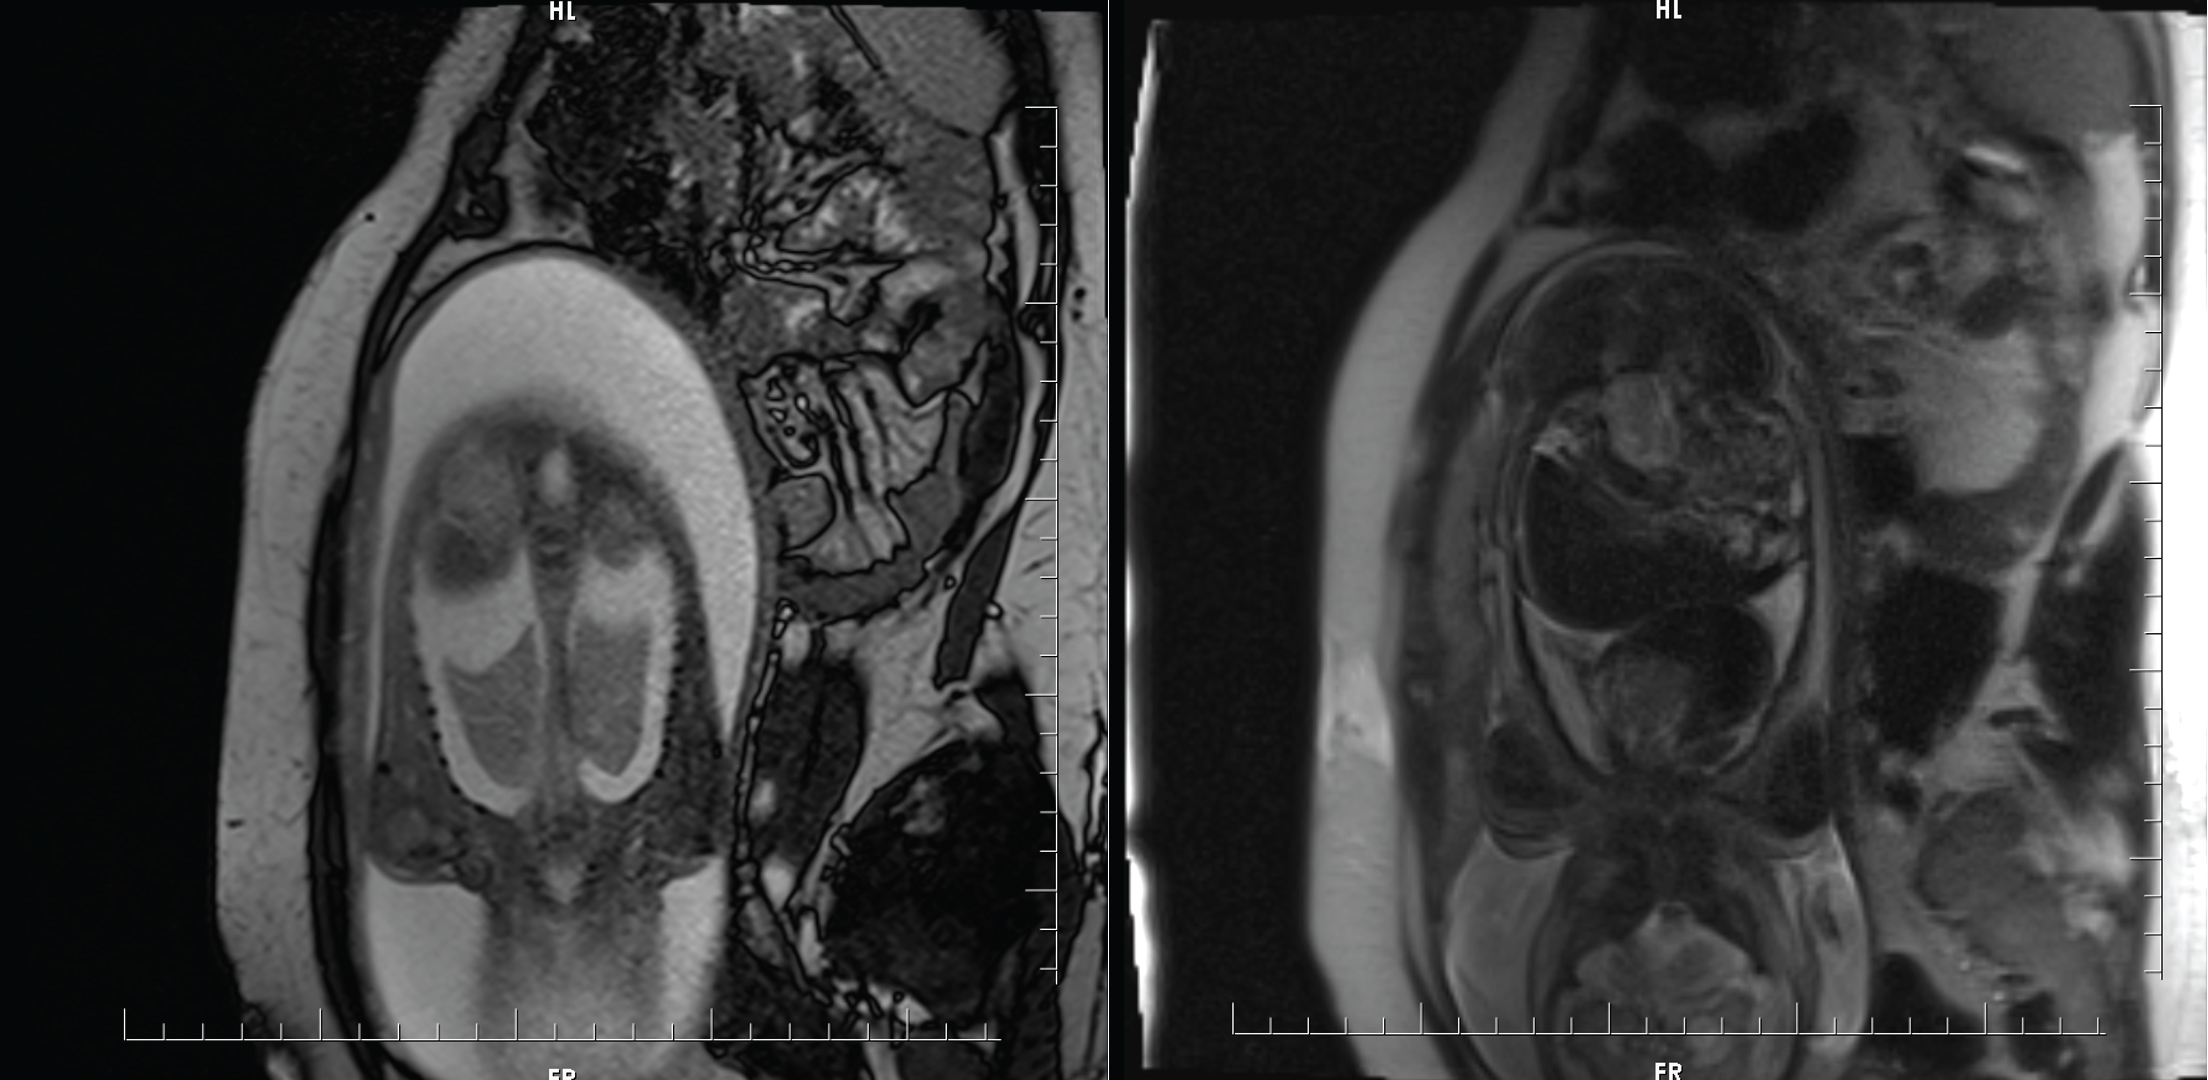

A 28-year-old woman, (gravida 1, para 0) at 31 weeks' gestation was referred to our clinic after adetailed antenatal ultrasound imaging revealed a mass in the mediastinum of the fetus. Fetal magnetic resonance imaging (MRI) revealed bilateral pleural effusion and a mass lesion in the anterior mediastinum, which was thought to originate from the right atrium (Figure 1). In the light of these findings the fetus was diagnosed with NIHF. It was decided to perform an EXIT procedure with bilateral tube thoracostomy and intubation. In the preoperative anesthesia examination of the mother, there was no additional systemic disease, ASA score was 2 and the patient's informed consent was obtained. In the operating room, after appropriate preoperative standard monitoring and positioning for left uterine displacement, the patient was intubated with rapid sequence induction without complications. Invasive arterial monitoring was carried out on the mother. Sevoflurane was administered at a MAC (Minimum Alveolar Concentration) value of 2.5-3.5 to ensure adequate depth of anesthesia and uterine relaxation. The mean arterial pressure (MAP) was kept above 65 mmHg for effective uteroplacental circulation, ephedrine and hydration were administered when hypotension occurred. After the newborn was delivered, bilateral tube thoracostomy was performed by pediatric surgeons without clamping the umbilical cord and the baby was intubated. During the EXIT procedure, the newborn's peripheral oxygen saturation has ranged between 85-90% and the procedure spanned 6 minutes in total. Approximately 10 mL of fluid drained from the right thoracostomy and 15 mL of fluid from the left. The newborn's APGAR score was evaluated as 6/8. The newborn was transferred to the neonatal intensive care unit (ICU) after the initial evaluation and essential treatments. Following the clamping of the umbilical cord, oxytocin was administered to the patient to prevent uterine bleeding. The approximate amount of bleeding of the mother during the operation was 250 mL and blood product transfusion was not required. After the incision was closed, the patient was extubated and transferred to the ward.

Figure 1: MRI section showing bilateral pleural effusion on the left, and a mass lesion in the anterior mediastinum on the right.